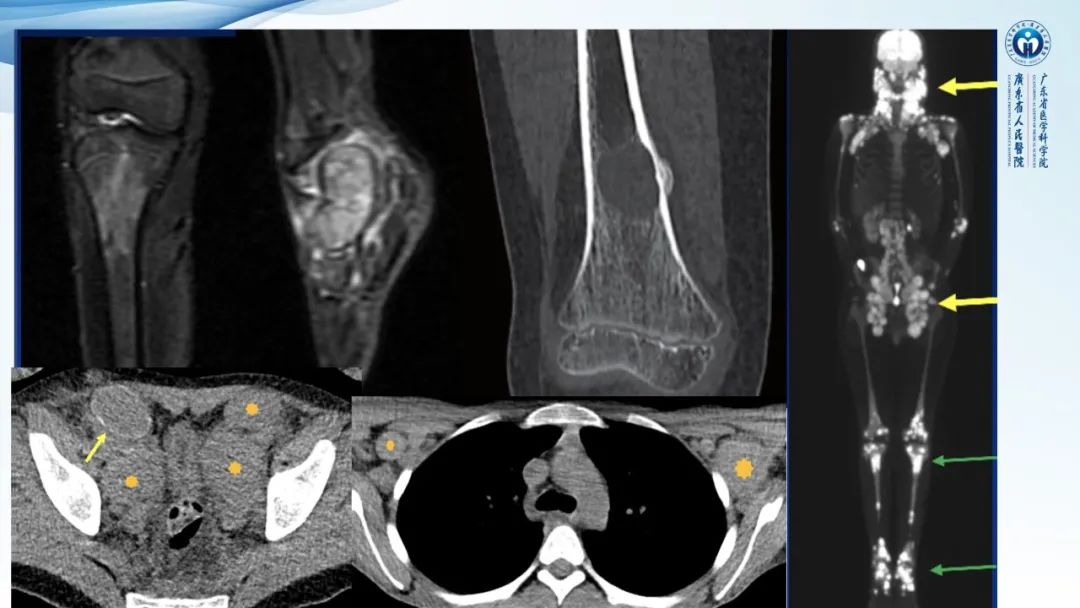

【病例】一例表现为弥漫中轴骨骨质增生硬化病变讨论-4